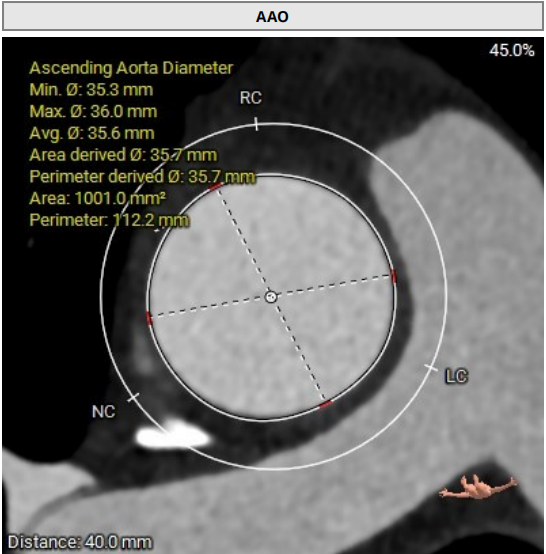

AAO:35.7mm